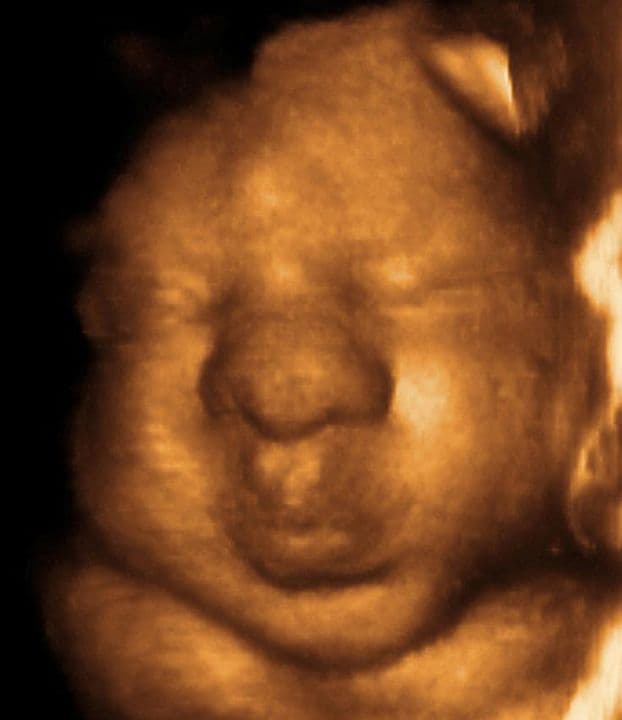

35 weeks and 6 days pregnant

Published: 29/08/16

Most babies will now be positioned longitudinally (lying straight up and down, with their head well in the pelvis). Even now, when space is limited in these final weeks, there is still time for the position to change to head down if your baby is bottom first (breech).